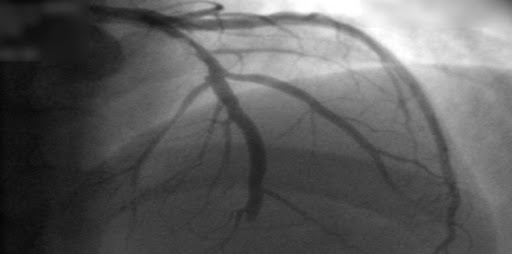

En los pacientes remitidos para cateterismo coronario por dolor torácico estable y con probabilidad intermedia de enfermedad coronaria antes de la prueba, la evaluación inicial por tomografía computada tuvo un riesgo de eventos cardiovasculares mayores similar a los de la evaluación invasiva, pero una menor frecuencia de complicaciones mayores relacionadas con el procedimiento. New England Journal of Medicine, 28 de abril de 2022.